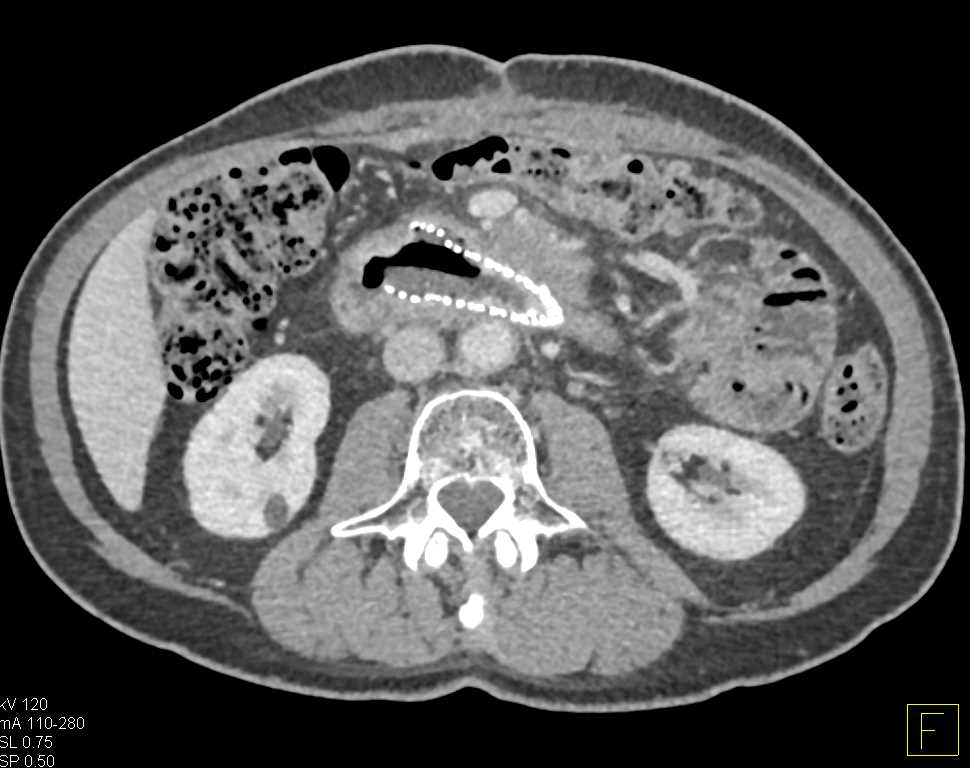

Hemorrhage in the Jejunum with Thickened Folds